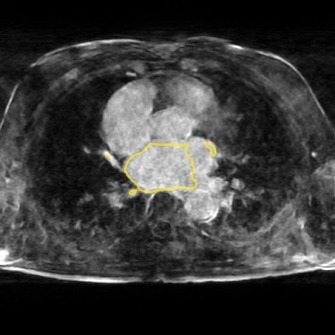

The following images show more samples for 8-fold undersampling. For each of the seven patients of the test set, a random slice showing the left atrium was selected. The contour of the predicted segmentation of left atrium is shown in yellow, the contour of the ground truth segmentation in red.